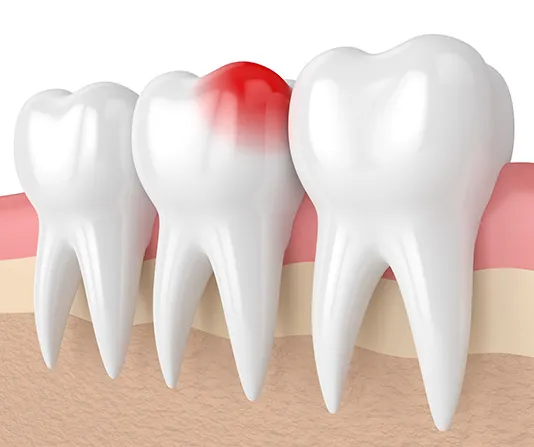

Dental implants provide a permanent, natural-looking solution for missing teeth. The implant is surgically placed in the jawbone, where it fuses with the bone for a secure and long-lasting fit. Implants help maintain bone density, restore function, and enhance aesthetics. With proper care, they can last a lifetime.